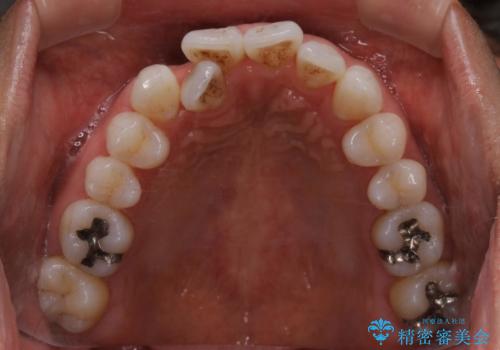

右上の前から2番目の歯が引っ込んで、下の前歯にはガタガタがありました。

上下の歯と歯の間を少量ずつ削りスペースを作り、インビザラインにて並べる計画としました。